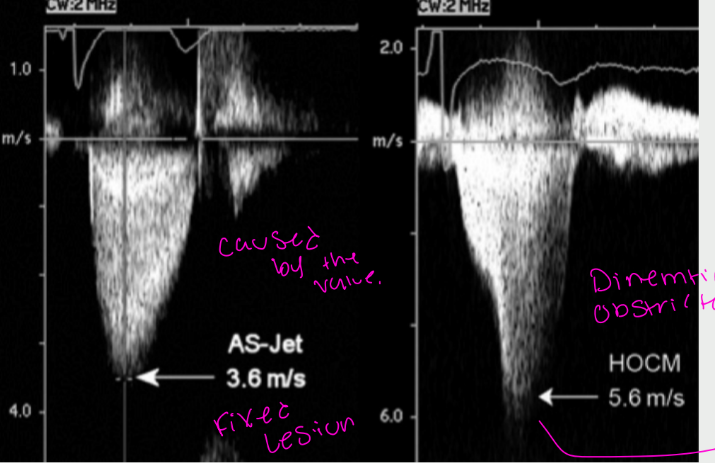

what is this showing

FIXED DOPPLER

SIGNAL VERSES

DYNAMIC

DOPPLER SIGNAL

more limitations with MR, MS, how do these affect and when uncontrolled systemic blood pressure is

Mitral regurgitation may reduce the

cardiac output

Mitral Regurgitation signal may be

mistaken for AS signal

what are the Differentials

Left Ventricular Obstructions can be

caused by the following...(3)

Fixed subvalvular obstruction (a

subaortic membrane or a muscular

subaortic stenosis)

⢠Dynamic subaortic obstruction

(hypertrophic cardiomyopathy)

⢠Supravalvular stenosis